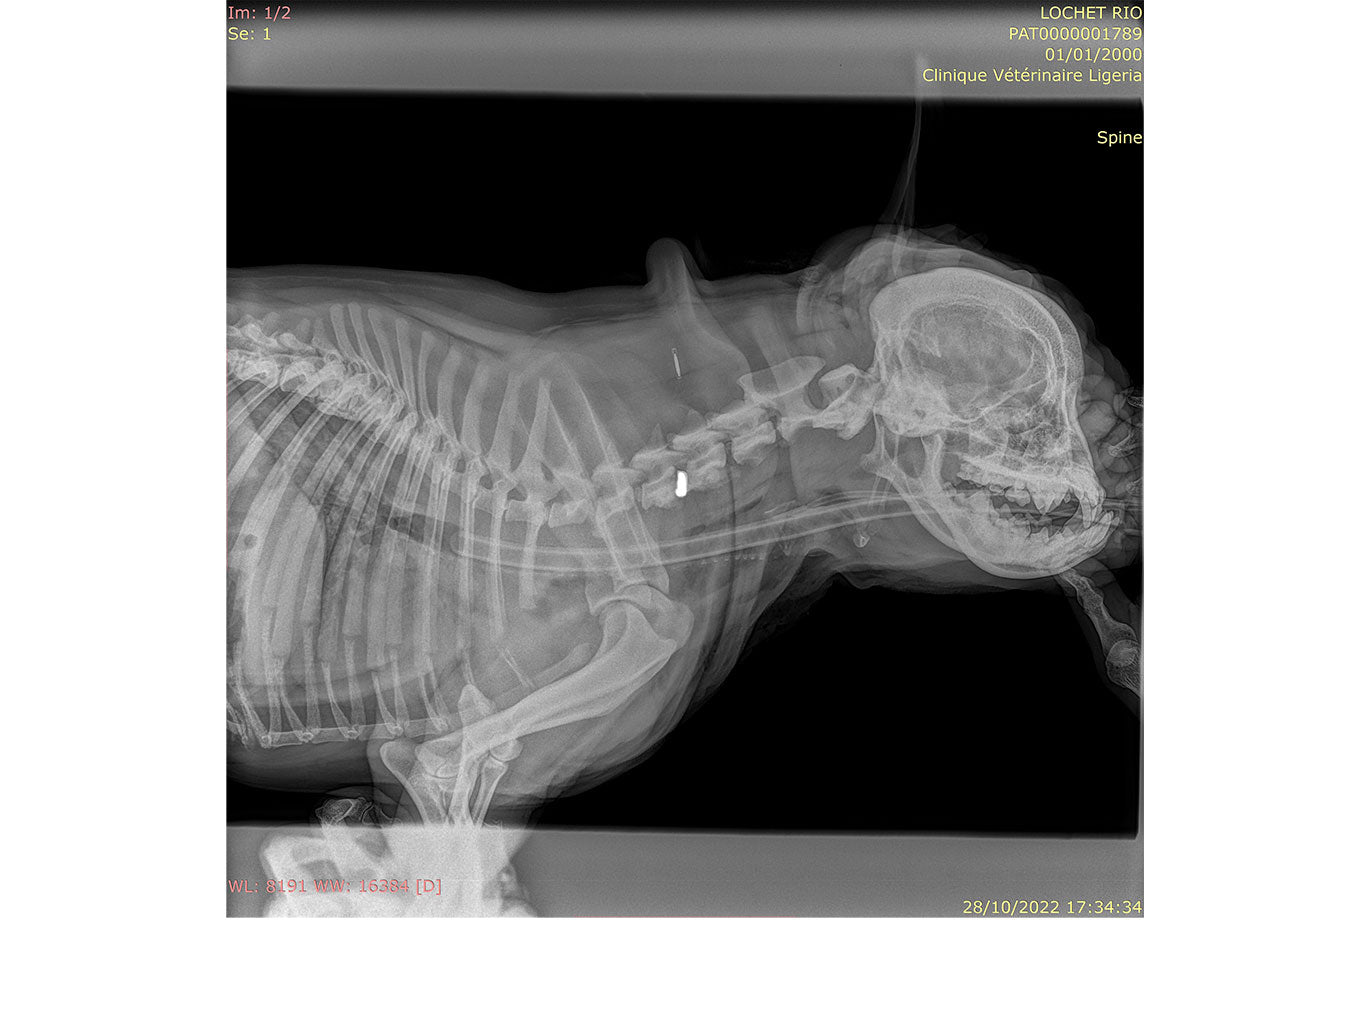

• Thoracic spinal stabilisation

// User Cases

Highlighting the cases of these products in real-life situations is vital to demonstrating their success. Below are cases studies of long-term follow up surgeries.